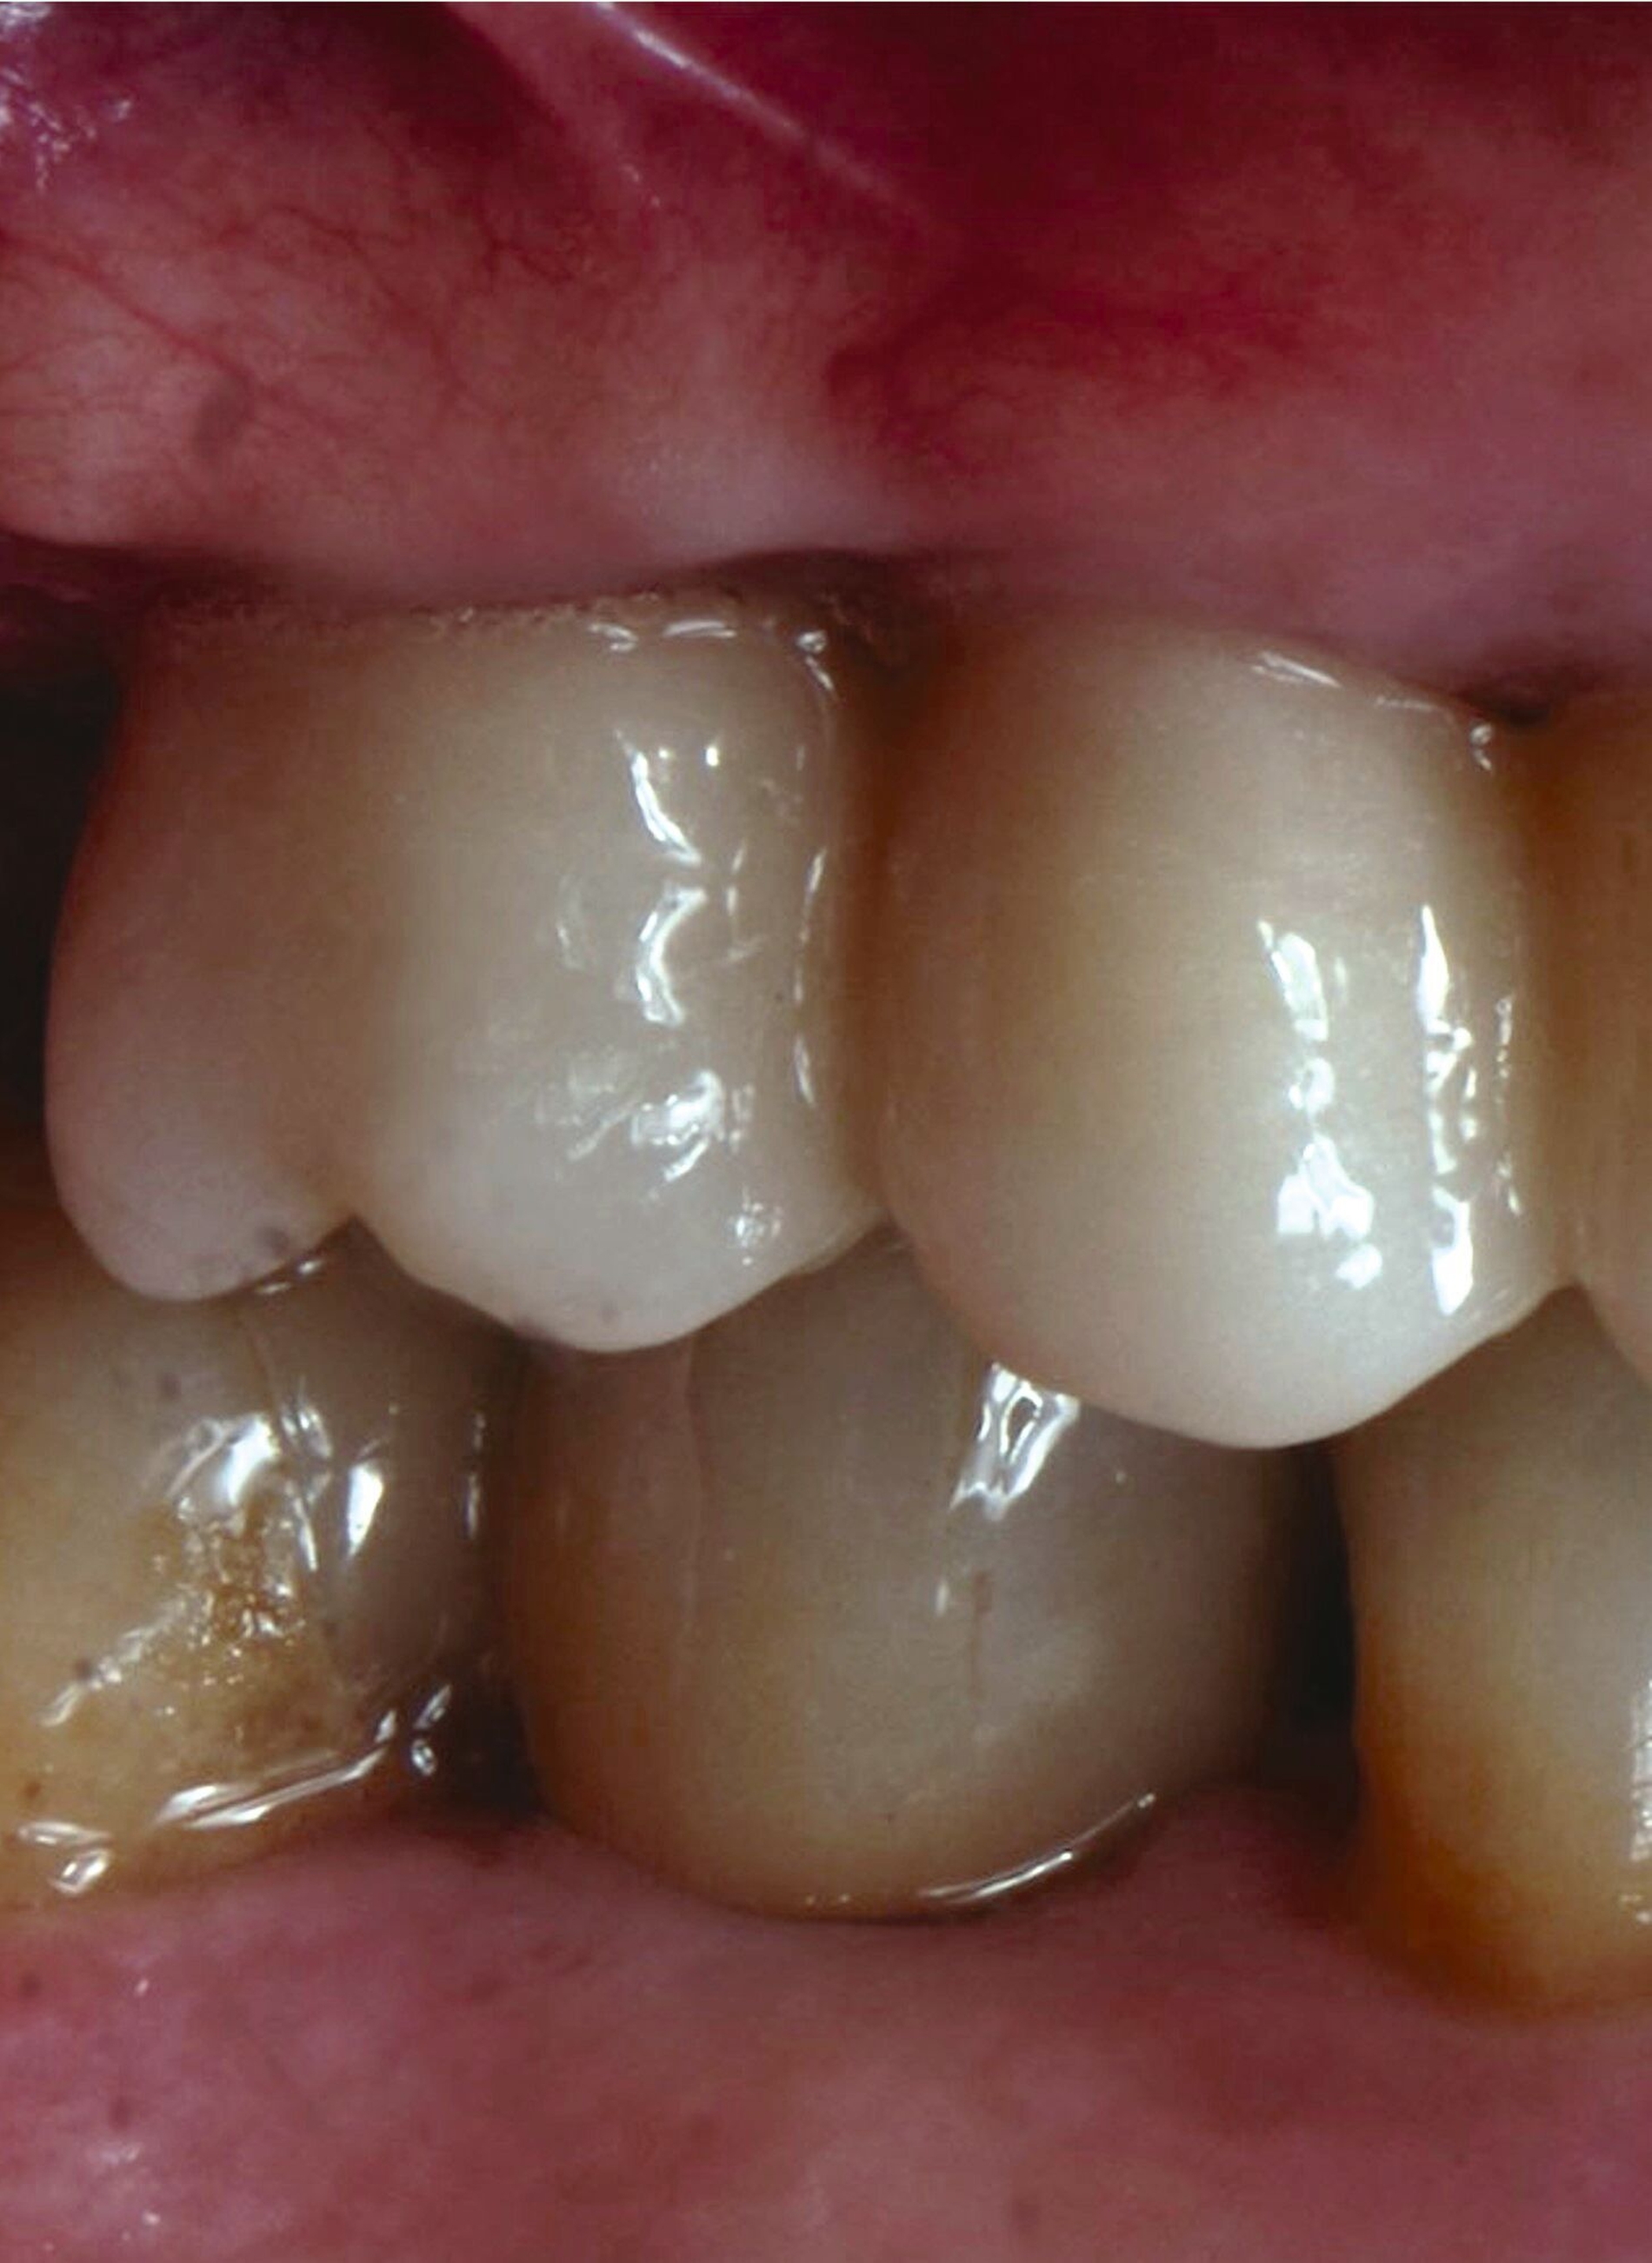

Eine zusätzliche Maßnahme, um das Weichgewebe zu optimieren, ist nicht notwendig und das angestrebte Okklusionskonzept kann umgesetzt werden, wobei die implantatprothetische Restauration nur minimal im Kontakt steht. Dies ist in vielen Fällen nur schwer umzusetzen. Wird die Restauration voll in statischer Okklusion belastet, bekommt die Restauration das Label A. Im vorliegenden Fall wird die Implantatkrone in gewisser Weise von den Nachbarzähnen geschützt, befindet sich aber dennoch in Okklusion (Abbildung 5). Für Implantatkronen, wie in diesem Fall, wird das Okklusionsschema so angepasst, dass die Shimstock-Folie im Schleifkontakt durchgehen kann. Situationen ohne okklusale Parafunktionen stellen ein geringes Risiko dar. Dann entscheidet der Zeitpunkt der Belastung über das Risiko, wobei spät und früh belastete Implantate dasselbe geringe Risiko haben. In unserem Fall zeigt der Patient Anzeichen einer Parafunktion, sodass den Unterkieferbewegungen und der okklusalen Morphologie der Restauration besondere Aufmerksamkeit gewidmet werden muss.